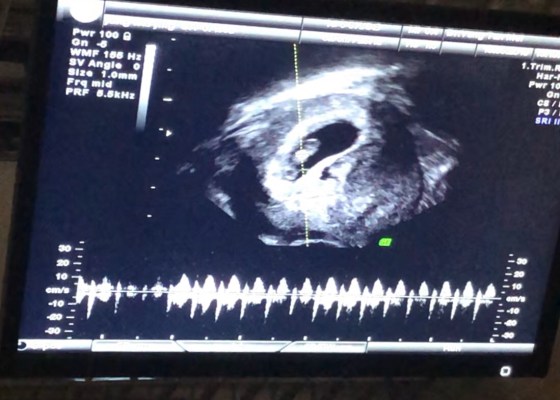

懷孕第 7 週:首次產檢!照到閃閃了!

" Size還是很小,0.98cm,醫生說是正常的。預產期沒變是12月28日。感謝,感謝… 第一次見到了,好感動,好神奇,自己肚子裏有另外一個人仔的心跳。(網上的媽媽會叫「照到閃閃」!)"